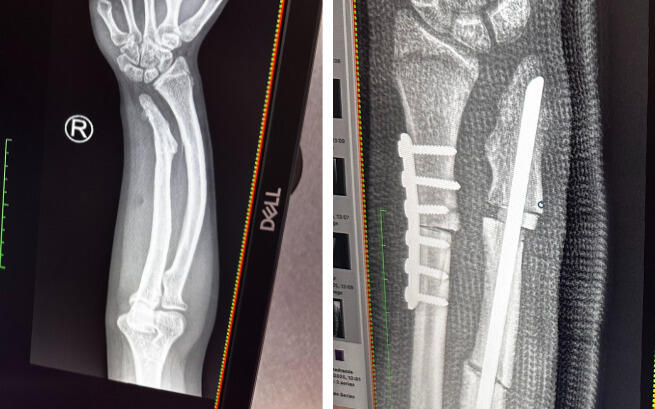

Kochani! – niestety, mamy złe wiadomości... W ostatnim czasie ponownie byliśmy na konsultacji w Warszawie, gdzie wykonano nowe badania RTG rąk i nóg naszej córki. Diagnoza dotycząca prawej ręki uległa pogorszeniu!

Podczas wcześniejszej operacji lekarze założyli płytkę na jedną kość oraz śrubę na drugą, jednak po zdjęciu gipsu okazało się, że śruba w okolicy łokcia blokuje wyprost ręki. Dodatkowo w tym miejscu kość od trzech miesięcy w ogóle się nie zrasta.

Na co dzień córka zmaga się z bólem i ograniczoną ruchomością ręki, co bardzo utrudnia jej funkcjonowanie, naukę oraz rehabilitację. Największym uciążeniem jest brak możliwości normalnego używania prawej ręki i ciągły dyskomfort. Lekarze zdecydowali o konieczności kolejnej, pilnej operacji zaplanowanej na 6 lutego – śruba zostanie usunięta i zastąpiona płytką, aby umożliwić prawidłowe zrastanie kości.